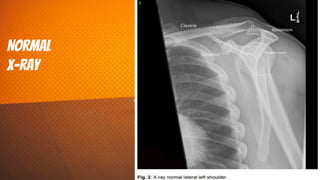

NorMal

x-ray